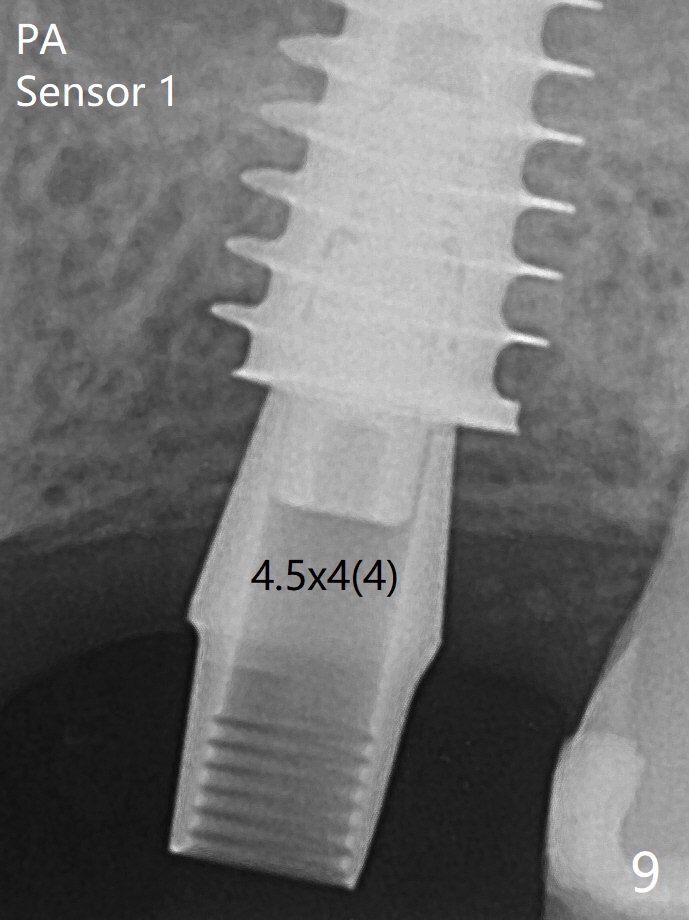

After extraction of the tooth #14 with palatal swelling (Fig.1 *), the septum (S in Fig.2) is found to be thin. Sequential osteotomy quickly deviates to the palatal socket. In spite of using Lindamann bur to remove the bone from the buccal portion of the osteotomy, the apical end of a 5x9 mm dummy implant slides into the palatal socket with the coronal end placed as buccal as possible for restoration (Fig.2 (poor trajectory)). Further use of Lindamann bur for buccal bone removal is not feasible, since the buccoapical portion of the osteotomy starts to be perforated with apparently intact sinus membrane. With insertion of Vanilla graft for sinus lift through the buccoapical portion of the osteotomy mentioned above, a 6x11 mm implant is placed with the same trajectory (Fig.2, <40 Ncm). With placement of a 6.5x4(3) mm abutment (off angle) and of Vanilla graft in the remaining sockets (Fig.2 *), periodontal dressing is applied. When the dressing is dislodged for the 2nd time (12 days postop with healing socket), an angled abutment 5x15 degree, 3 mm cuff, is placed and a provisional is fabricated. There is no sign of sinus infection. The provisional and angled abutment become loose without sinus infection 2 months postop. A 5.5x3 mm healing abutment is placed with light tenderness. If this case turns to be failure, do not stick an immediate implant from potentially infected socket into the sinus in the future. The socket appears to heal 11 months postop (Fig.4). Later a 5x4(3) mm abutment is placed for final restoration. The palatal margin is low. The abutment screw is loose <2 months post cementation, probably due to deep placement and poor trajectory (buccal). It becomes loose again 4 months later. Prior to retightening, a 6 mm profile drill is used. BW shows no bony interference (Fig.5 (opposing tooth occlusal wear; bruxism)), while PA shows the buccal bone, suggesting poor trajectory. The abutment is loose for the 3rd time 17 months post cementation. When the crown/abutment is removed, the hex is worn. After proximal reduction, the crown/abutment feels to be unable to be re-seated. When the crown is sectioned, the abutment itself is incompletely seated (Fig.7,8). The mesial crest appears to interfere with seating (Fig.8). When the 5.2x3 mm dummy abutment is seated, the buccal margin is subgingival, while the palatal one supragingival, suggesting the buccally tilted implant (guided surgery essential). A 4.5x4(4) mm pair abutment seems to be seated completely (Fig.9). The hex of the 5x4(3) mm abutment is worn, but the abutment seems to be able to be seated completely (Fig.11), although not so crisply (easily) as the unworn one clinically. Return to Upper Molar Immediate Implant, Prevent Molar Periimplantitis (Protocols, Table), Armaments Screw Xin Wei, DDS, PhD, MS 1st edition 06/26/2018, last revision 12/20/2020